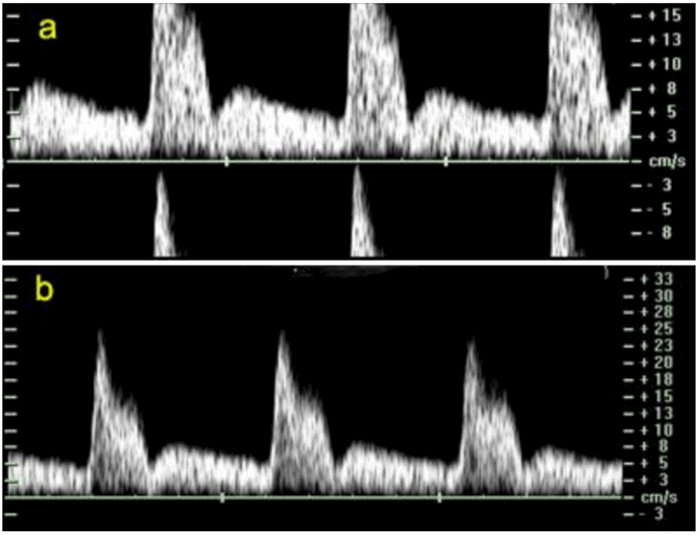

Оценка маточных артерий во втором триместре (Рис. 2)

Рис. 2. Кривые скоростей кровотока в маточной артерии, полученные трансабдоминальным доступом во втором триместре беременности. Нормальный (а) и патологический (б) спектр; обратите внимание на наличие дикротической выемки (стрелка) на спектре КСК (б).